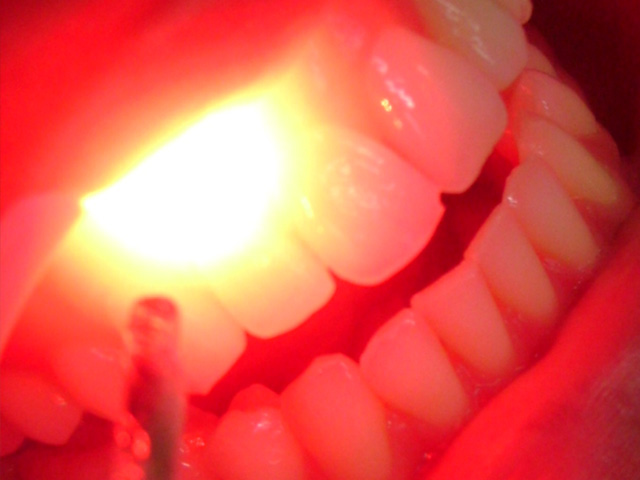

Laser Portatil

A laserterapia de baixa intensidade tem uma gama muito grande de uso na odontologia, aftas lesões herpéticas, hipersensibilidade dentinária, transtornos articulares, dor e edemas, leva a uma redução da dor e acelera a recuperaçõa tecidual.

O laser hoje é considerado um método não invasivo sendo um auxiliar terapeutico com efeito antiinflamatório e reparação tecidual.Imediatamente após a primeira aplicação se nota uma diminuição da dor.